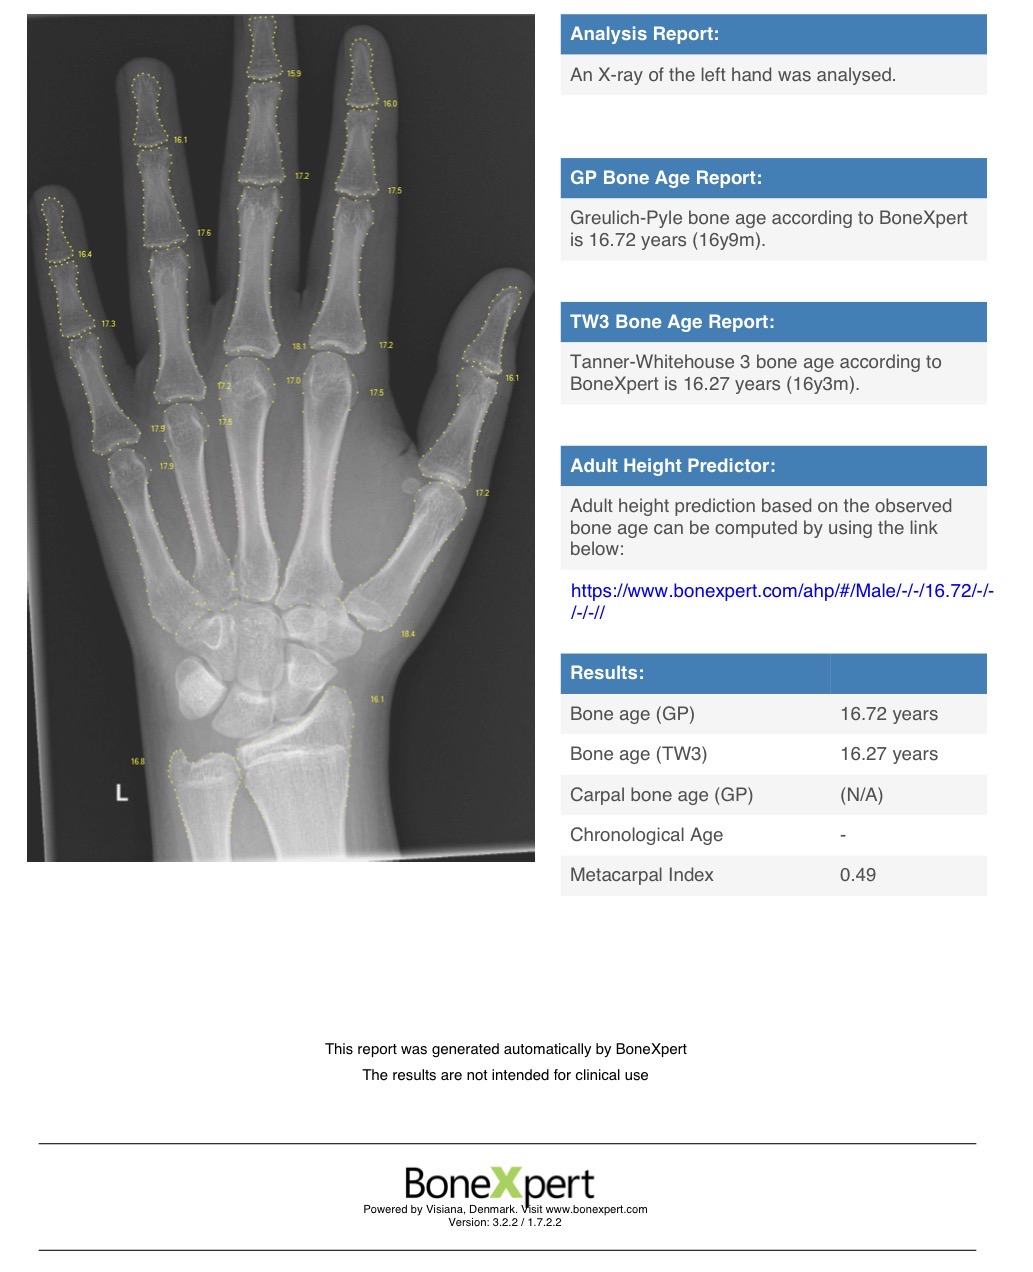

Heres my scan. Chronological age 16.5.

Is HGH worth it? I would be running exemestane along with it.

Obviously height wont be the main factor as that train has long departed.

Is minimal height growth possible? Are the other effects worth pinning HGH instead of pinning test e/p?